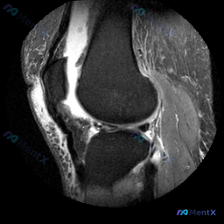

刚整理了一份膝关节MRI读片病例,分享一下完整分析思路。 病例影像基本信息 这是一张膝关节MRI矢状位图像,用户提问是否存在半月板异常,我们来一步步分析: 影像基础评估结果 1. 骨骼与关节: 股骨远端、胫骨近端皮质连续,无明显骨折,无明显骨髓水肿、软骨下囊肿,关节间隙和对合关系基本正常 2. 关节...